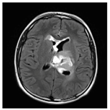

Among patients included in the PEDIAMODECAN program (seven DIPGs and four tHGGs (thalamic high-grade gliomas)), we selected four cases that were mismatch repair proficient and harboring the driver histone mutation H3.3 K28M. We were able to derive four PDCLs out of seven DIPGs and two PDCLs out of four tHGGs. Among the four DIPG PDCLs, we had only two H3.3-K28M-mutated tumors. The patient ages ranged from 9 to 18 years old. The clinical reports, including immunohistochemistry results, are summarized in Table 1. MRI radiological data showed that DIPGs and tHGGs invaded the pons or thalamus, respectively, at diagnosis, with a localized tumor enhancement after gadolinium injection on T1-weighted and T2-weighted FLAIR (fluid-attenuated inversion recovery) sequences. The immunohistochemical analyses were performed for Ki67, GFAP (glial fibrillary acidic protein), p53, EGFR (epidermal growth factor receptor), PTEN (phosphatase and tensin homolog), Olig2 (oligodendrocyte transcription factor 2), and HIF-1α (hypoxia inducible factor 1 alpha) biomarkers.

Table 1.

Clinical characteristics of four pediatric H3F3A-K28M-mutated high-grade gliomas. BT: brain tumors; HGG: grade IV glioma; DIPG: diffuse intrinsic pontine glioma; Iri/Beva: Irinotecan/Bevacizumab; ADC: apparent diffusion coefficient measured within T2-weighted injected sequences. Ki67, HIF1 (hypoxia inducible factor 1), GFAP (glial fibrillary acidic protein), EGFR (epidermal growth factor receptor), PTEN, and Olig2 stainings (% of positive cells in tumor specimen) were used. Tumors for which analyses were unavailable are designated NA (not available).* Stupp protocol with a total of 12 courses of temozolomide was used in post-radiotherapy.